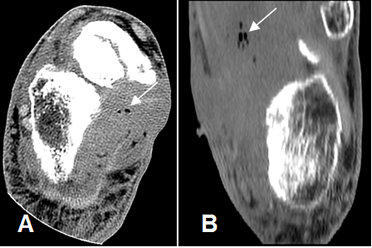

Fig 128 A. Osteomielitis del calcáneo.

A: TAC axial en ventana de tejido y B: en ventana de hueso. Cambios inflamatorios en los tejidos blandos (Flecha delgada), con orificio de fístula medial. (Flecha gruesa).

C: TAC reconstrucción coronal. Erosión del calcáneo, por osteomielitis. (Punta de flecha).